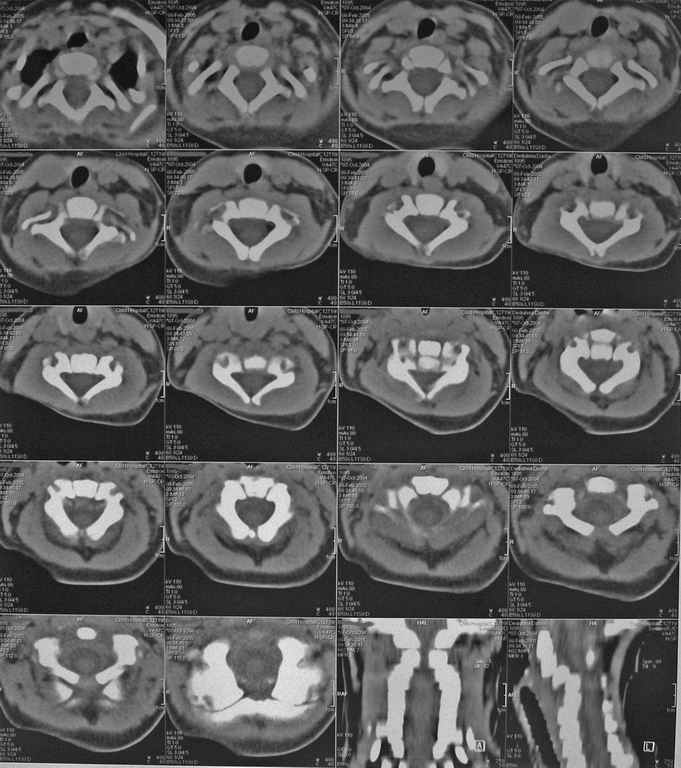

Девочка 5 месяцев, дочь коллеги, врача-анестезиолога, тетрапарез, в ногах спастический в руках - вялый, усугубившийся после "мануальной терапии".

Данные рентгена,КТ и МРТ прилагаются. Кроме того, имеется двухсторонний врожденный вывих бедра.По совокупности данных - болезнь Ларсена.В шейном отделе - дисплазия и гипоплазия суставных отростков С3-С5 с передним подвывихом и антелистезом, патологическим кифозом и стенозом позвоночного канала до 55% от исходного (5 мм при исходном 9 мм). Spina bifida occulta в 5 сегментах, в том числе расщепление задней дуги атланта, агенезия его передней дуги. Признаки спинальной компрессии и диффузной миелопатии на уровне стеноза.Вопрос - возможно ли в таком нежном возрасте оперативное лечение и вообще, какая должна быть тактика ?